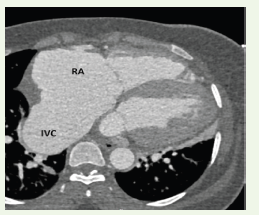

Figure 3:Axial ECG-gated contrast-enhanced CT image at the level of

the cardiac base demonstrating marked dilatation of the right atrium (RA)

and enlarged inferior vena cava (IVC), consistent with right-sided volume

overload.

Clinical manifestations depend on the size of the defect and the rapidity of shunt formation. Small unruptured aneurysms may remain asymptomatic, whereas rupture commonly produces an acute left-to-right shunt leading to dyspnea, volume overload, and signs of heart failure [2,7]. Chronic shunting may result in progressive right atrial enlargement, pulmonary hypertension, and secondary valvular dysfunction. In the present patient, right atrial dilatation, inferior

vena cava enlargement, and pulmonary arterial dilatation were

evident on CT, reflecting significant hemodynamic impact.